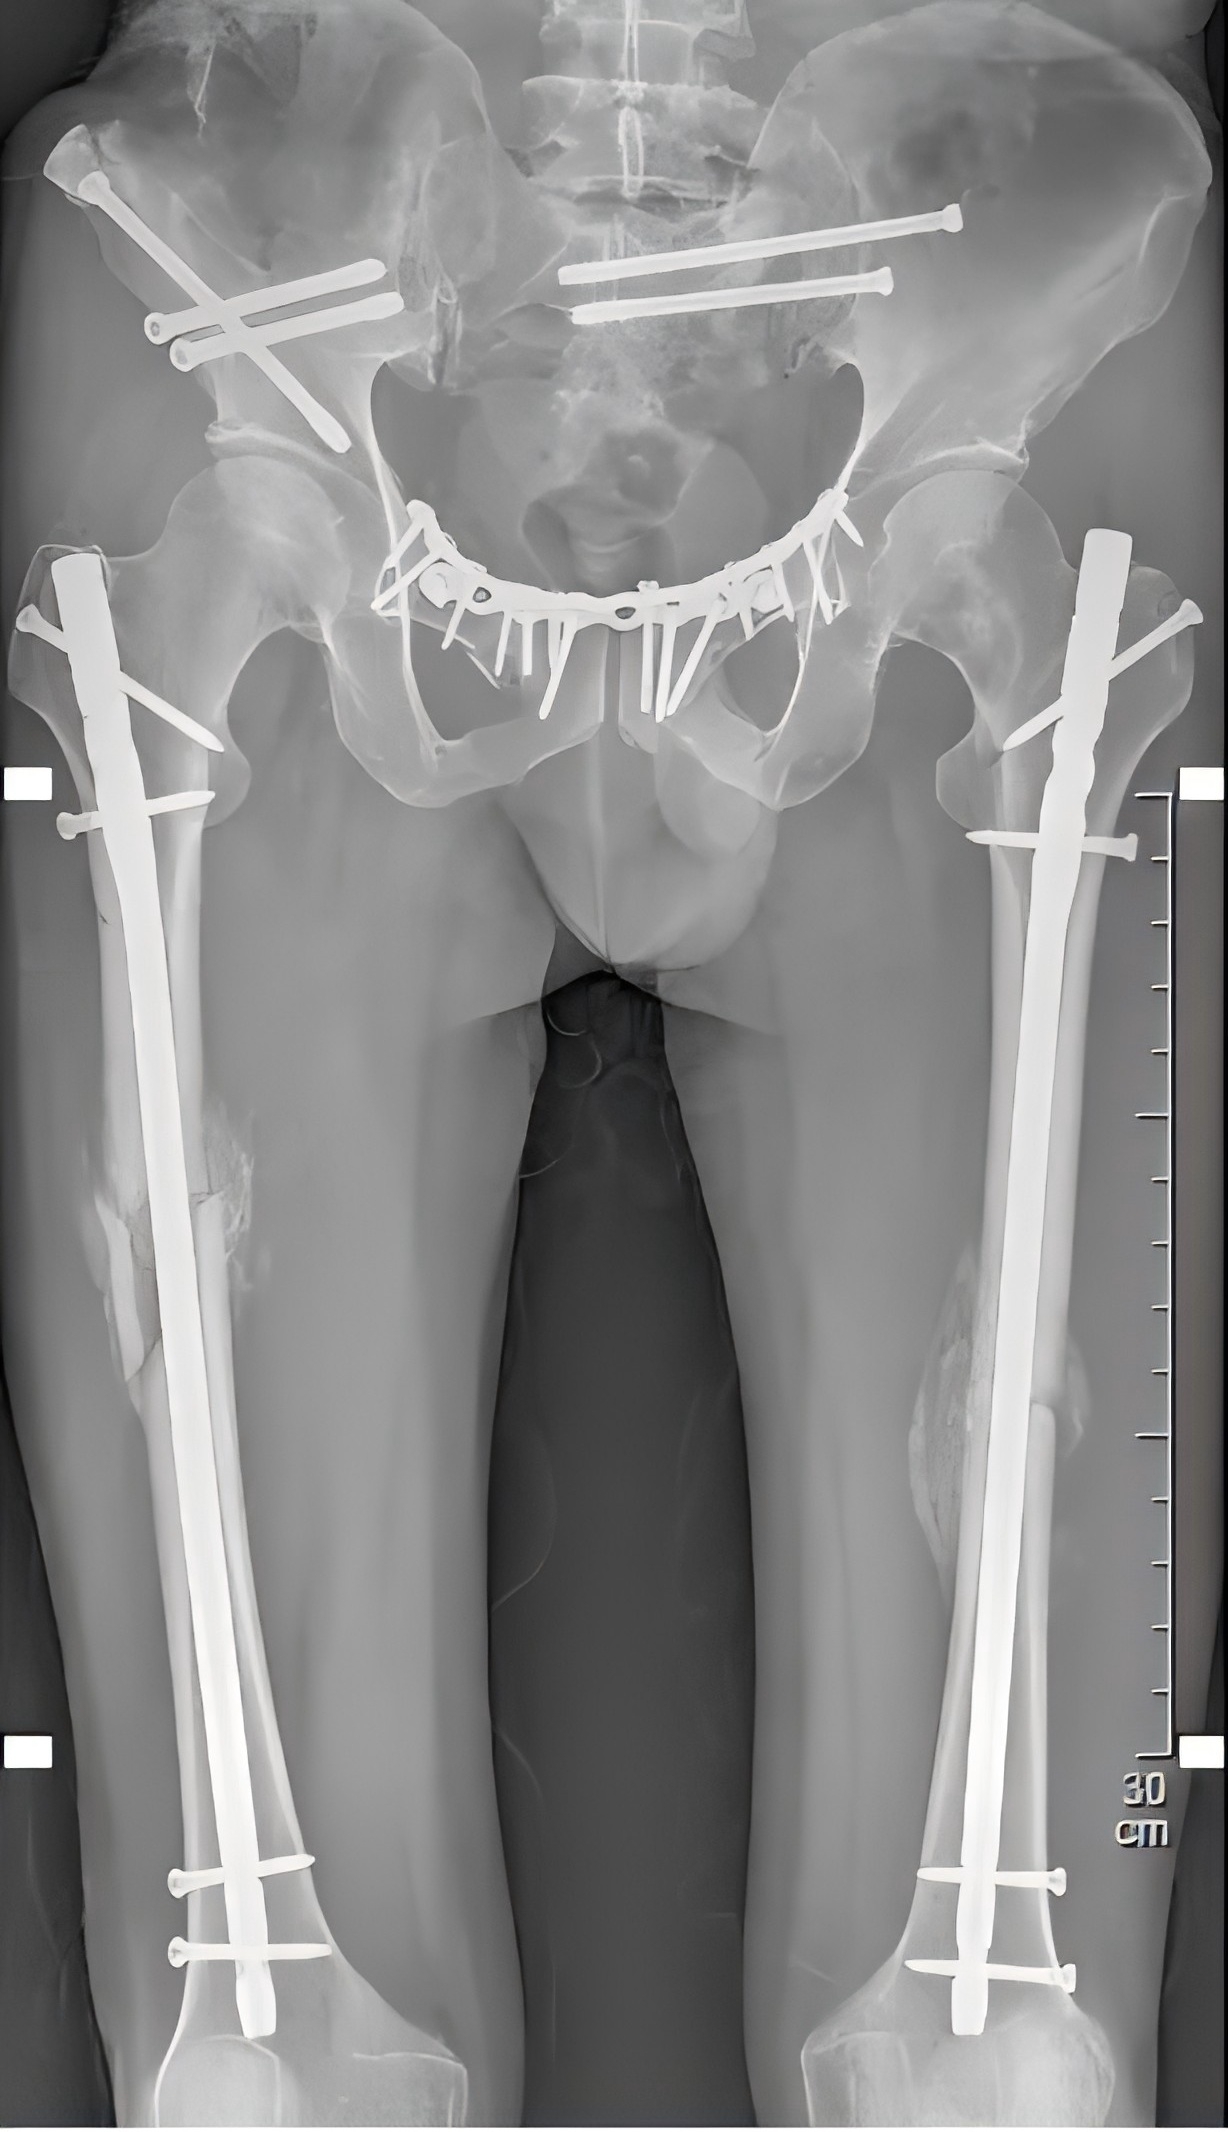

近日,江陰市人民醫(yī)院敔山灣院區(qū)骨科三科成功救治了一名因重物砸傷導致嚴重骨盆及多部位骨折的危重患者。通過精準施行微創(chuàng)手術(shù)和科學康復訓練,患者入院28天后便順利出院,創(chuàng)造了快速康復的“江陰速度”。

全力以赴救治重傷患者

2月28日,48歲的戴某不慎被重物(重量約為2噸)砸傷,導致多發(fā)性骨盆骨折、右側(cè)粉碎性髂骨骨折、雙側(cè)股骨骨折、右側(cè)腓骨骨折等多處損傷,尤其是骨盆處幾乎“散架”,患者失血性休克,生命垂危。

殷小軍團隊基于損傷控制理念,為患者量身定制了微創(chuàng)手術(shù)方案。手術(shù)分為兩期進行:待患者生命體征穩(wěn)定后,一期先行骨盆及一側(cè)股骨骨折微創(chuàng)內(nèi)固定治療;二期行另一側(cè)股骨骨折微創(chuàng)內(nèi)固定手術(shù)。

醫(yī)療團隊僅用了11天,便為患者完成了多發(fā)骨折的手術(shù)治療。手術(shù)后一周,患者即可進行半臥、翻身活動,既減輕了護理難度,也增強了患者戰(zhàn)勝疾病的信心。

(患者術(shù)后X片)

經(jīng)過精心治療和科學照護,患者逐漸恢復了健康。

入院28天后,患者便順利康復出院。

術(shù)后1個月,復查顯示患者的骨折處愈合情況良好,大量骨痂形成。

術(shù)后40多天,患者已能下床活動,平穩(wěn)地行走了。